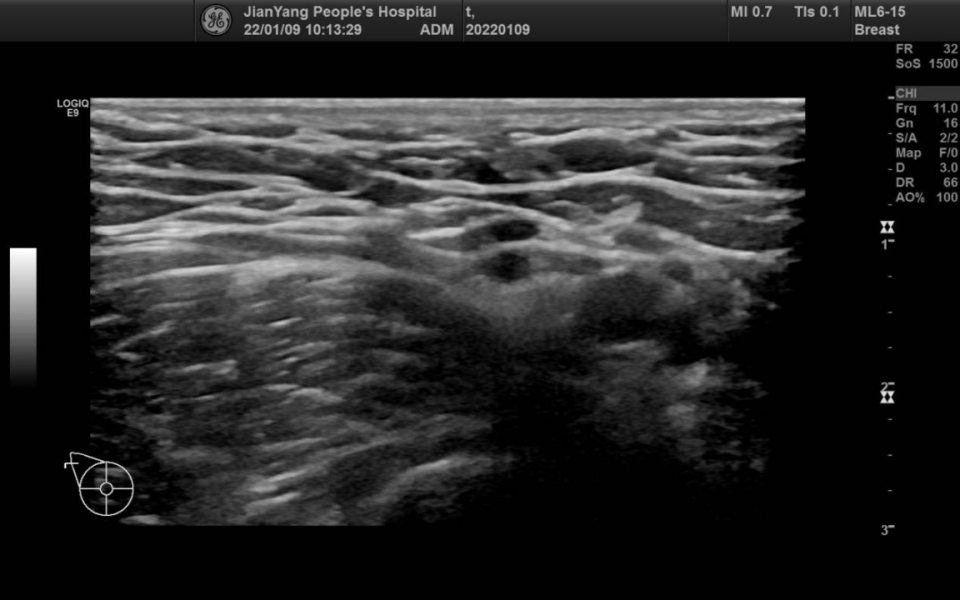

申请超声检查图像如下:

图片图 2 左乳 2 点钟方向肿物

两侧乳房切面形态轮廓正常,层次清楚,腺体回声不均匀,左乳 2 点钟方向距乳头约 20 mm 处可见范围约 28.3 mm x 22.4 mm x 28.1 mm 的低回声团,略呈分叶状,边界清楚,内可见不规则无回声区,其内可见较多条状血流信号。

双乳导管未见明显扩张征像。CDFI:余腺体内未见异常血流信号。

超声提示:左乳低回声团 BI-RADS 4A 类

MBC 多见于绝经后妇女,肿块较大,超声特征多表现为不均匀低回声,边缘光整,形态不规则,平行于皮肤,无钙化或微小钙化,后方回声无改变或增强,伴或不伴腋窝淋巴结转移,Adler 分级 Ⅱ~Ⅲ 级多见,阻力指数多>0.7。与间叶化生癌相比,鳞状细胞癌多表现为直径较大、呈囊实性回声、腋窝淋巴结无转移。